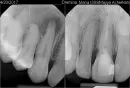

Мой сын случайно головой ударился о мой клык. Боли я почти не чувствовала, но со временем заметила шишечку на десне. Но не сразу придала значения, так как зуб полностью был здоров. Я не знала, что от такого незначительного удара корень зуба может умереть. Врач промыл канал, лекарство поставил всего на две недели, а потом закрыл канал. Чего я не ожидала, делала в другой стране. Шишка со щеки спала, но неожиданно через два почти месяца появилась вновь. За один день увеличилась и лопнула. Пришла к врачу, сделали снимок 3Д. По снимку видно, что уже кости нет. Инфекция распространилась ещё больше, как я понимаю, что уже захватывает соседний зуб. Мне предлагают сделать резекцию корня зуба. Понимаю, что альтернатива - это только удаление зуба. Так как живу в стране, где стоматология ужасно дорогая, и решается вопрос ехать в Россию, чтобы вылечить. Если есть, конечно, смысл.

Резекция верхушки корня может помочь в сохранении зуба, но думаю в связи с таким обширным воспалением зуб все же лучше удалить.

Соседний зуб пока можно попробовать пролечить, путём депульпирования и заведения лекарства за верхушку корня.